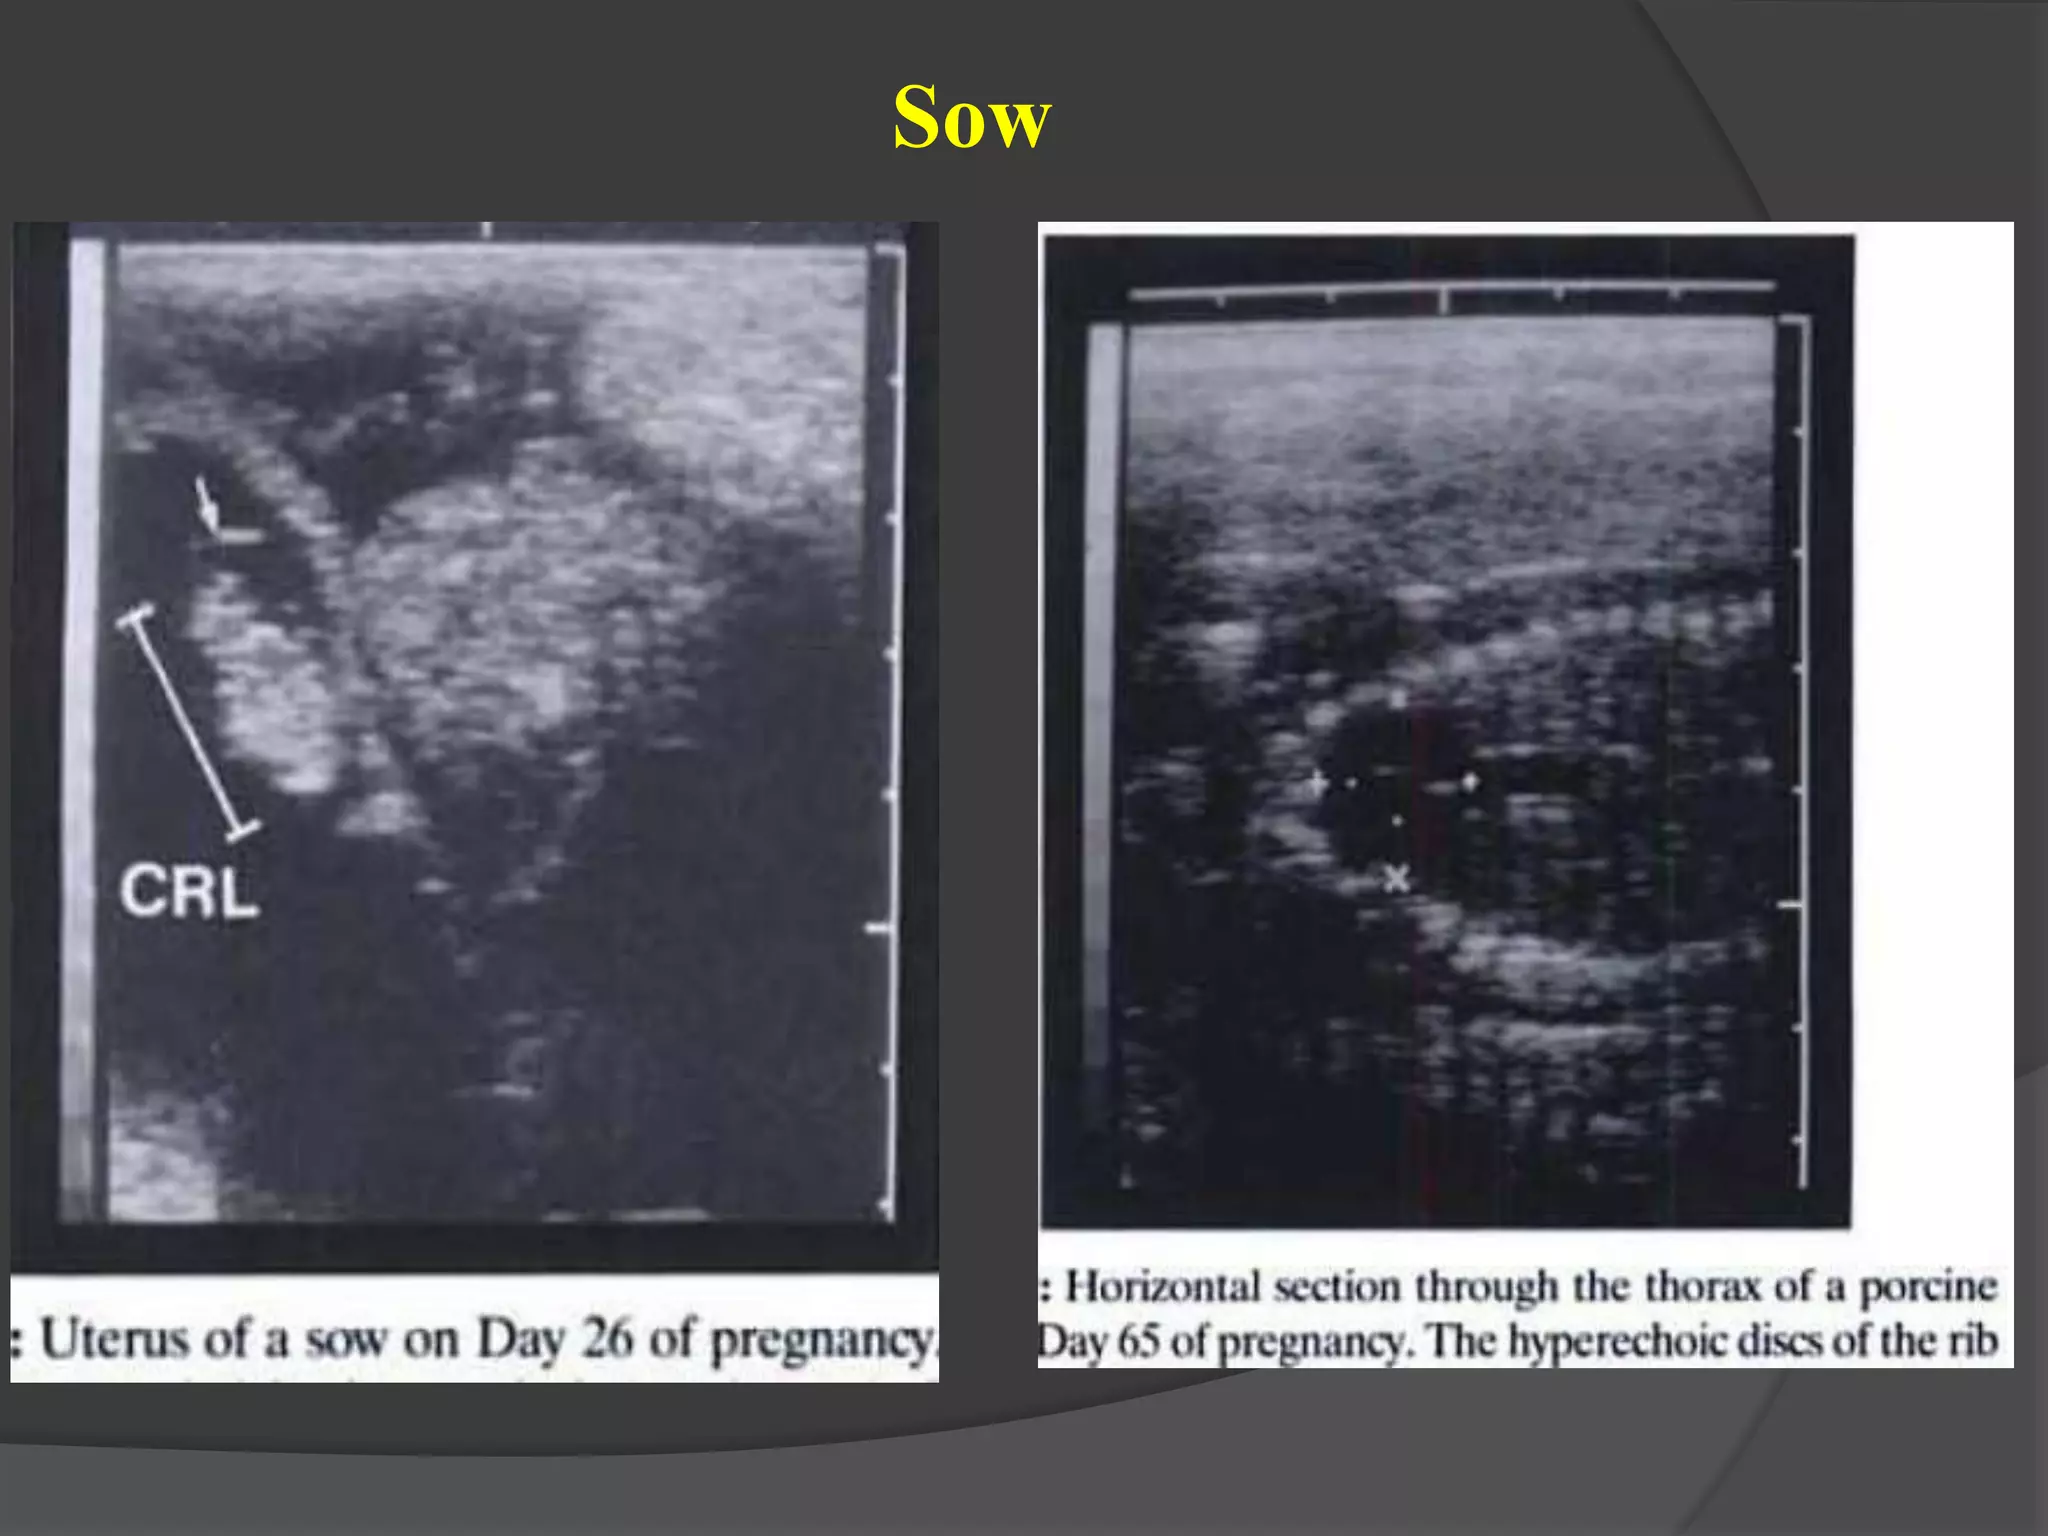

Fetus on day 59 with the fi rst view of the ribs embryonic mortality observed at day

Sow

30 - day- old embryo 40 - day - old embryo Fetus on day 59 with the fi rst view of the ribs embryonic mortality observed at day 30 Cow